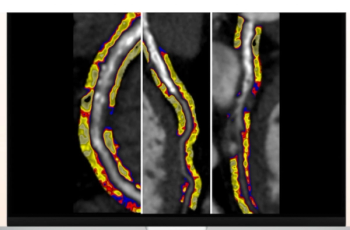

Cardiac CT angiography may provide insights on common post-op complications of left atrial appendage closure, ranging from peri-device leaks to device-related thrombus, according to research presented at the American Roentgen Ray Society (ARRS) conference.